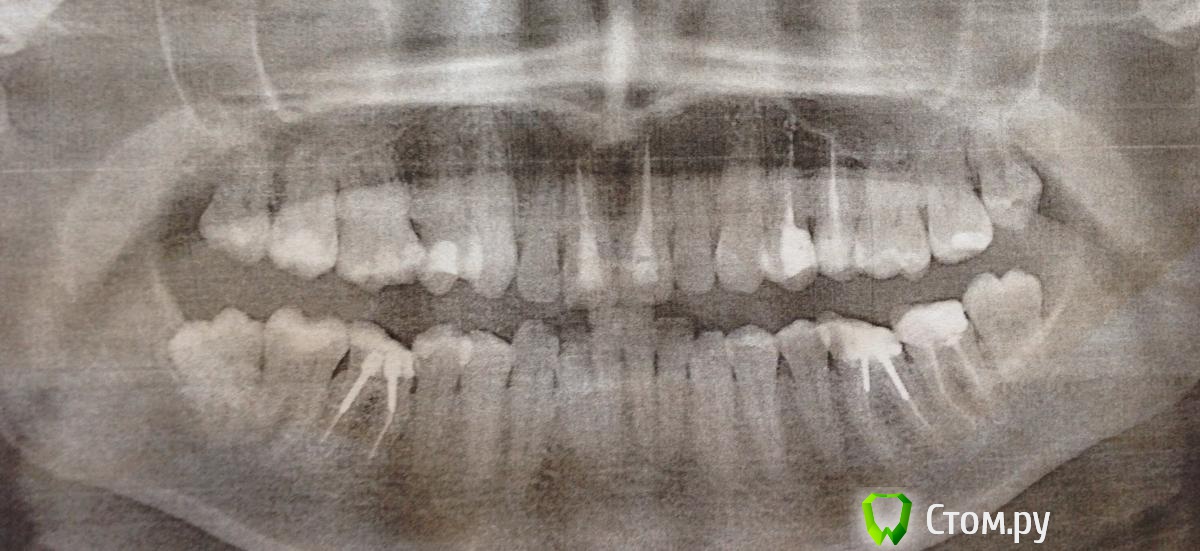

Калинина Опубликовано 31 мая, 2014 Поделиться Опубликовано 31 мая, 2014 Добрый день! Прошу Вас помочь мне с выбором варианта лечения. Была у 3 ортодонтов:1. Первый врач предложил удалить мне четыре восьмерки и сделать временные коронки на 2 шестерки на нижней челесте2. Второй врач предложил удалить одну восьмерку в нижнем ряду с правой стороны и поставить временные коронки на шестые зубы меньшим размером чем есть сами зубы, за счет этого добиться сводного места, а так же освободить место за счет сепарации всех зубов3. Третий не рекомендовал прибегать к сепарации, т.к. это влечет к образованию кариеса. Предложила удалить 6-е зубы(т.к. они "депульпированные") в нижних рядах, сохранив восьмерки при этом, но тогда процесс лечения растягивается вдвое. А сверху удалить пятерку с лева (с права пятерки нет, удалили в связи с тем, что она не стояла в ряду, вылезла в сторону), удалить восьмерки с верху, развернуть шестерку справа. И второй вариант удалить 4 четверки. Но как дальше себя будут вести 8 в будущем, если удалят к примеру 6.Помогите пожалуйста, что мне делать?! О себе мне 29 лет.Если сможете посоветовать грамотного ортодонта буду очень благодарна. Ссылка на комментарий